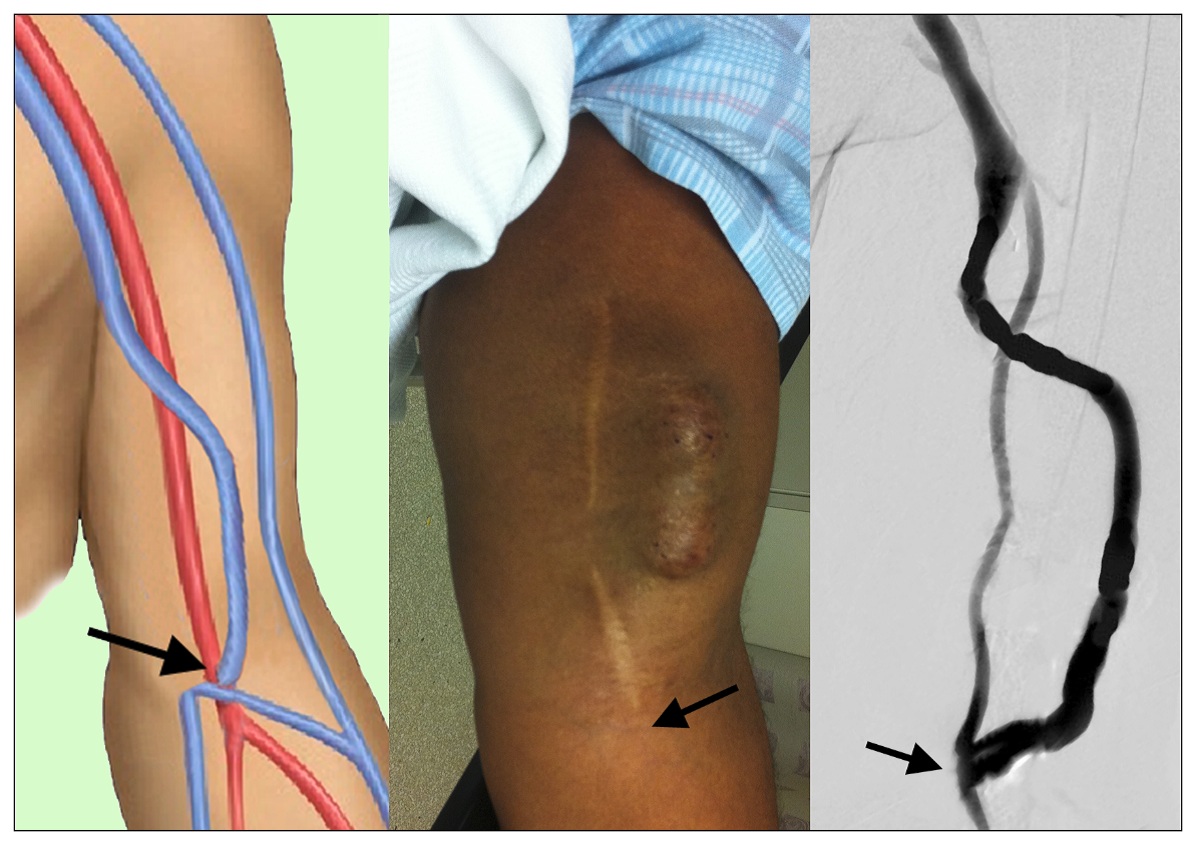

Figure 3

Brachial-basilic anastomosis anatomy (at arrows) shown in three ways: the artist’s drawing (left panel), an aneurysmal basilic vein transposed (BVT) with needle puncture scars, being used for dialysis (middle panel), the arrow indicates the anastomosis site, and a contrast angiographic display (right panel)